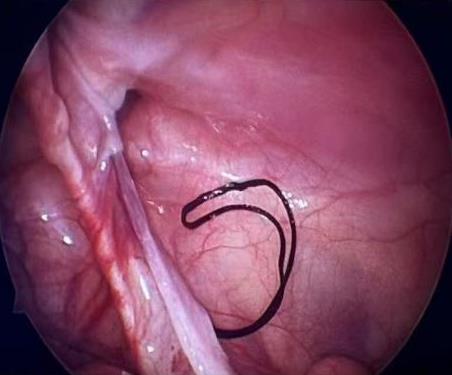

摘要:目的 探讨常规切开Latarjet手术、关节镜下Latarjet手术、关节镜下Bankart修复联合Remplissage手术在肩关节复发性前脱位(RASD)合并肩胛骨关节盂骨缺损 > 15%及啮合性Hill-Sachs损伤中的应用效果及安全性。方法 回顾性分析该院2022年1月-2024年12月收治的65例RASD合并肩胛骨关节盂骨缺损15%~25%及啮合性Hill-Sachs损伤患者的临床资料,根据手术方法的不同,分成A、B和C组;其中,A组实施常规切开Latarjet手术(n = 18),B组实施关节镜下Latarjet手术(n = 21),C组实施关节镜下Bankart修复联合Remplissage手术(n = 26)。比较3组患者手术情况、手术前后相关量表评分[视觉模拟评分法(VAS)、Constant-Murley肩关节评分和加州大学洛杉矶分校(UCLA)肩关节评分等]和肩关节活动度,以及术后并发症和复发情况。结果 手术时间:B组长于A组和C组(P < 0.05),A组长于C组(P < 0.05)。术中出血量和住院时间:A组多于或长于B组和C组(P < 0.05),B组多于或长于C组(P < 0.05)。3组疼痛VAS评分:术后1、6和12个月都低于同组术前(P < 0.05)。术后1和6个月疼痛VAS评分:A组均高于B组和C组同期(P < 0.05)。术后1个月疼痛VAS评分:B组高于C组(P < 0.05)。术后12个月疼痛VAS评分:3组差异不明显(P > 0.05)。比之同组术前,A组术后6和12个月,B组和C组术后1、6和12个月,UCLA肩关节评分均明显升高(P < 0.05)。术后1个月UCLA肩关节评分:A组低于B组和C组(P < 0.05),B组低于C组(P < 0.05)。术后6和12个月UCLA肩关节评分:3组患者差异均不明显(P > 0.05)。比之同组术前,A组术后6和12个月,B组和C组术后1、6和12个月Constant-Murley评分均明显升高(P < 0.05)。术后1个月Constant-Murley肩关节评分:A组低于B组和C组(P < 0.05)。术后6和12个月Constant-Murley肩关节评分:3组患者无明显差异(P > 0.05)。3组患者前屈上举活动度:术后12个月都大于同组术前(P < 0.05)。术后12个月前屈上举活动度:3组患者无明显差异(P > 0.05)。术前、术后12个月体侧外旋、外展90°外旋活动度:A组和B组组内和同期组间均无明显差异(P > 0.05)。C组体侧外旋、外展90°外旋活动度:术后12个月小于术前(P < 0.05)。术后12个月体侧外旋、外展90°外旋活动度:A组和B组均大于C组(P < 0.05)。术后并发症发生率和复发率:3组患者无明显差异(P > 0.05)。结论 常规切开Latarjet手术、关节镜下Latarjet手术、关节镜下Bankart修复联合Remplissage手术治疗RASD合并肩胛骨关节盂骨缺损15%~25%及啮合性Hill-Sachs损伤,均能有效改善肩关节功能及缓解疼痛,但两种肩关节镜手术的创伤更小,术后恢复更快。